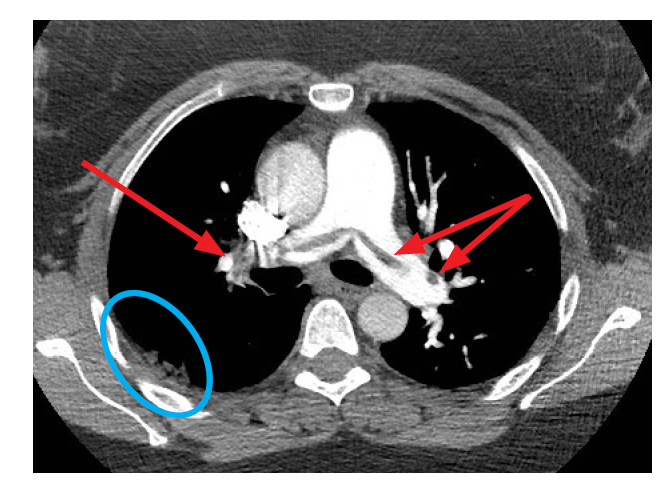

What is the red arrows?

PE